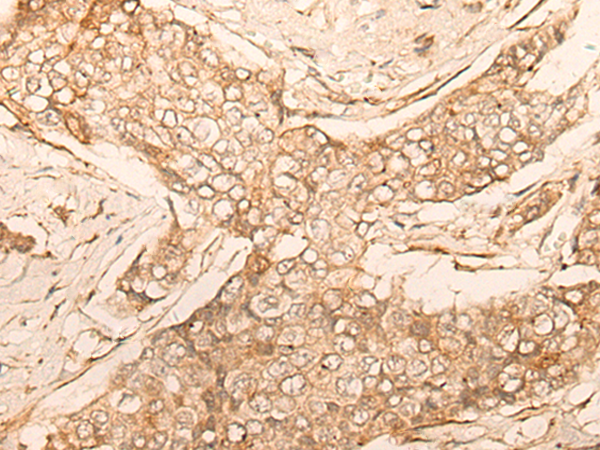

IHC positive control: |

Human esophagus cancer and Human breast cancer |